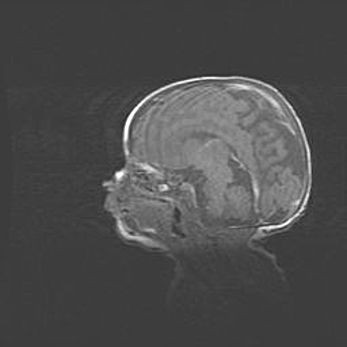

Мальформация Денди-Уокера. Киста задней черепной ямки.

Агенезия мозолистого тела.

Возраст: 2,5 месяца

Вес: 2420 г

Пол: женский

Окружность головы: 37 см

Срок гестации: 32 недели

Мальформация Денди—Уокера — редкий вид патологии ЦНС, представляющий собой врожденный порок развития каудального отдела ствола и червя мозжечка, ведущий к неполному раскрытию срединной (Мажанди) и латеральных (Лушка) апертур IV желудочка мозга. Для этогно синдрома характерна триада симптомов: гипотрофия червя мозжечка и/или полушарий мозжечка, кисты задней черепной ямки, гидроцефалия различной степени. В 70% случаев порок сочетается и с другими аномалиями головного мозга, в частности с агенезией мозолистого тела.